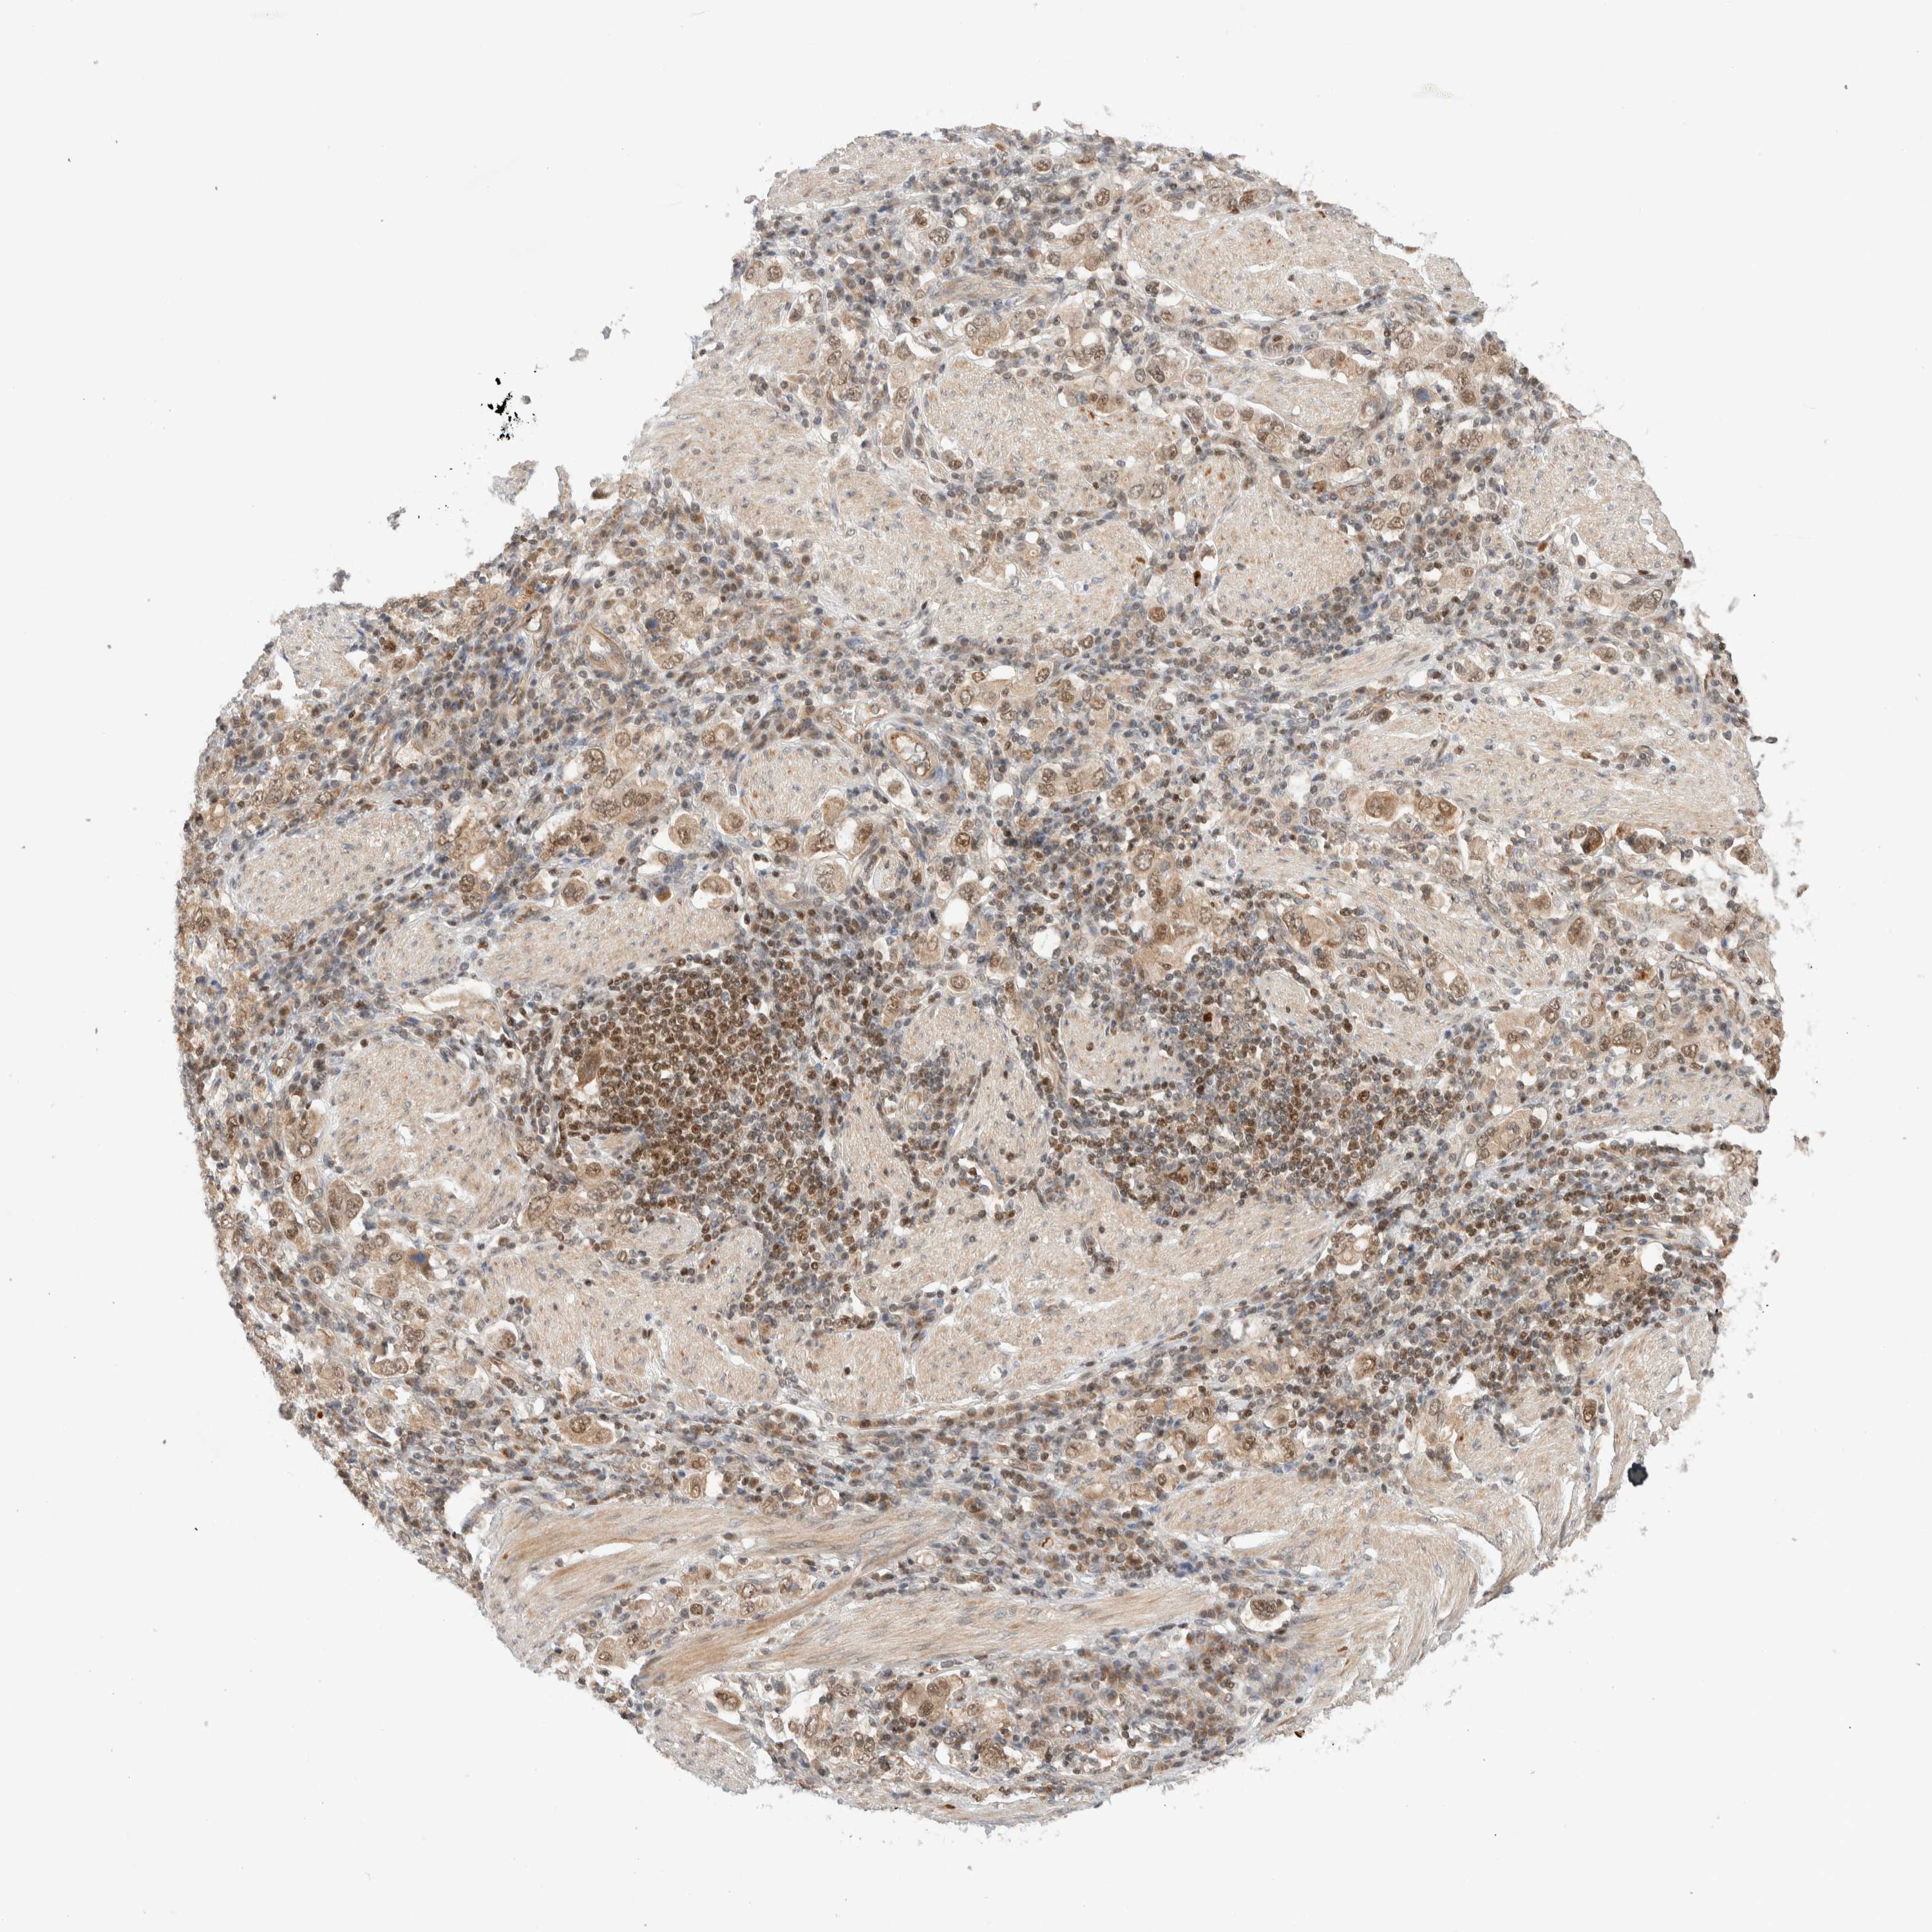

STOMACH CANCER - Protein expressioni

A mouse-over function shows sample information and annotation data. Click on an image to view it in a full screen mode. Samples can be filtered based on level of antibody staining by selecting one or several of the following categories: high, medium, low and not detected. The assay and annotation is described here.

Note that samples used for immunohistochemistry by the Human Protein Atlas do not correspond to samples in the TCGA dataset.

Antibody stainingi

Antibody staining in the annotated cell types in the current human tissue is reported as not detected, low, medium, or high, based on conventional immunohistochemistry profiling in selected tissues. This score is based on the combination of the staining intensity and fraction of stained cells.

Each image is clickable and will lead to virtual microscopy that enables deeper exploration of all samples and also displays staining intensity scores, fraction scores and subcellular localization as well as patient and tissue information for each sample.

Antibody HPA023708

Staining

High

Medium

Low

Not detected

Intensity

Strong

Moderate

Weak

Negative

Quantity

>75%

75%-25%

<25%

None

Location

Nuclear

Cytoplasmic/membranous

Cytoplasmic/membranous,nuclear

Adenocarcinoma, NOS